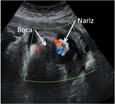

En el tercer trimestre de embarazo la mano del bebé se aprecia con gran nitidez, como podemos observar en esta imagen ecográfica. Hasta se llegan a esbozar los pliegues de los dedos y las marcas digitales. Impresiona ver este ultrasonido, que corresponde a un bebé de unas 32 semanas de gestación.

Ecografía 3D de mano fetal en el tercer trimestre de embarazo